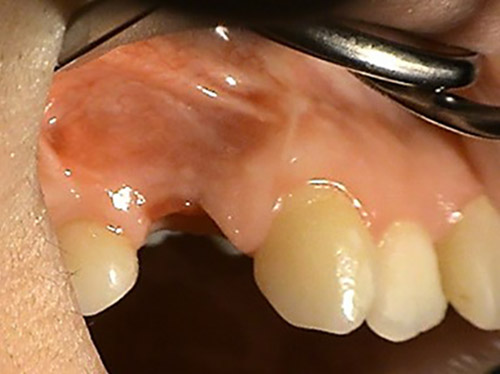

3. PHASE – prosthetic fabrication of temporary crown on implant